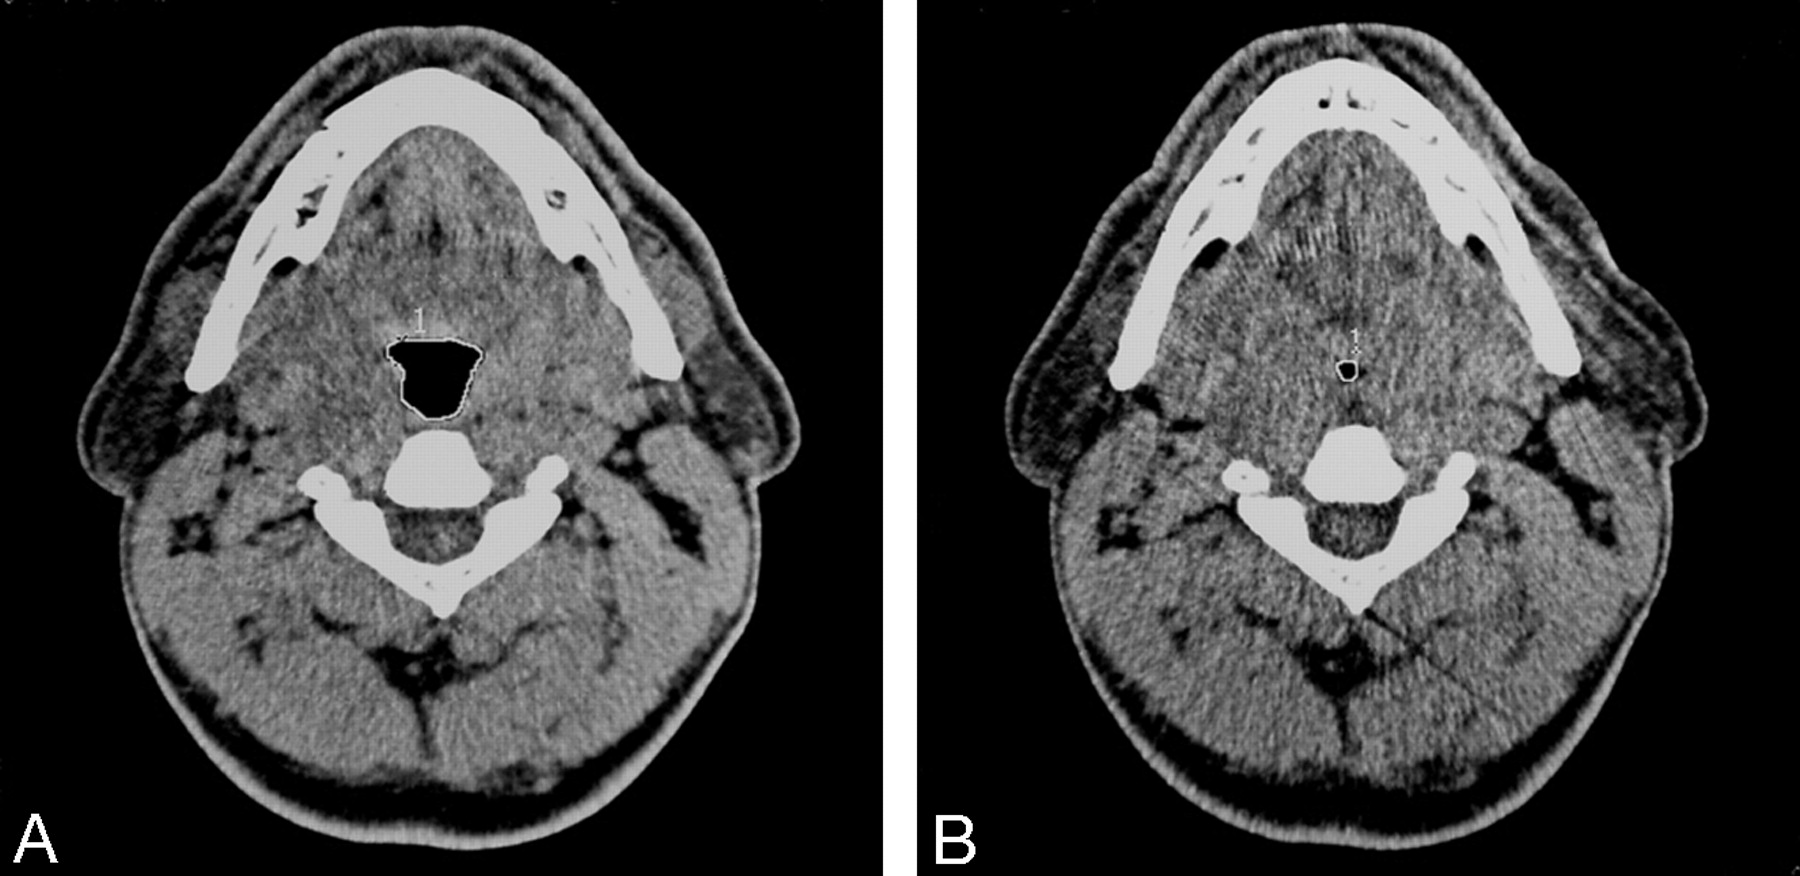

Head and neck CT (Toshiba Express TSX-011A; Toshiba, Tokyo, Japan) was performed in all patients while they were awake in the supine position with their heads in a neutral position (120 kV; 50 mA; section thickness, 5 mm; scanning time, 1 second; field of view, 400 mm; display matrix, 512 × 512 pixels). A lateral scout view was taken first to determine and standardize the level of the scans. Because the area of the pharyngeal airway changes during the respiration, we performed dynamic scans at the same anatomic level. Cross-sectional area of the airway at the level of oropharynx (level 1, tip of uvula) and hypopharynx (level 2, under the hyoid bone) were obtained in each phase of quiet tidal breathing, at the end of forced inspiration and at the end of forced expiration. Cross-sectional areas of the upper airway were manually measured by the same technician using electronic calipers (Fig 1A, -B).

A, Cross-sectional image of a patient at the level of uvula in tidal breathing. B, The significant narrowing at the same level in forced expiration is seen. The region of interest (white line) was used to assess total cross-sectional areas in each image.